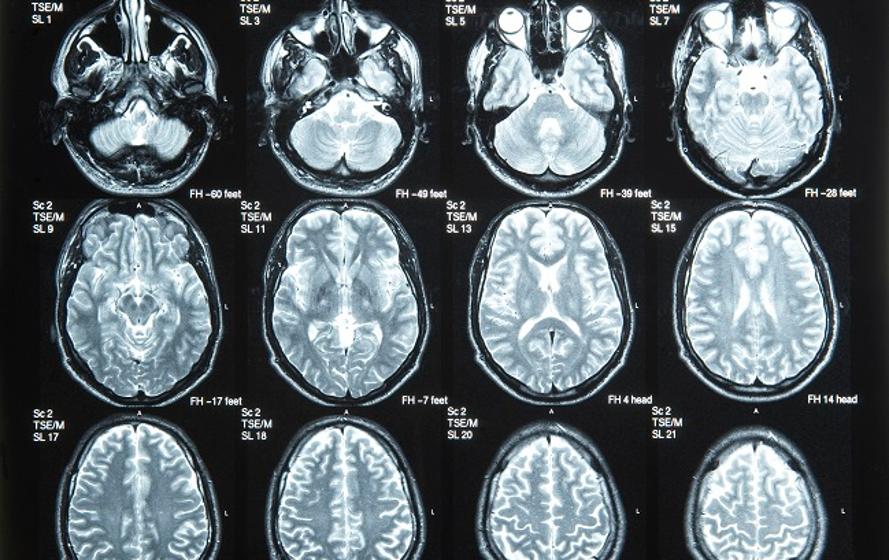

영국 브리스톨대 Shelley J. Allen 교수팀은 16S rRNA 차세대 염기서열분석(NGS) 분석 결과 알츠하이머 환자의 부검 뇌에서 박테리아가 발견됐다는 연구 결과를 Frontiers in Aging Neuroscience 최신호에 발표했다.

Allen 교수팀은 영국 뇌은행에 보관돼 있는 알츠하이머 환자 8명과 알츠하이머가 없는 고령자 6명의 뇌 샘플 NGS 분석결과를 비교했다.

(출처: Frontiers in Aging Neuroscience, 영국 브리스톨대 Shelley J. Allen 교수팀 논문)

그 결과 정상 뇌보다 알츠하이머 뇌에서 7배 많은 박테리아가 발견됐고, 알츠하이머 뇌에서도 방선균류(Actinobacteria)가 프로테오박테리아(Proteobacteria)보다 10배 이상 많은 것으로 나타났다.